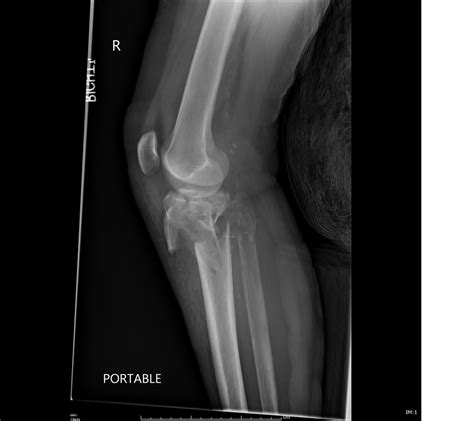

To evaluate the medial tibial plateau, orthopedic specialists utilize a combination of clinical examinations and diagnostic imaging. Because the knee joint is surrounded by soft tissues, X-rays alone may not reveal the full extent of an injury.

X-ray Best for identifying fractures, major bone displacement, and joint space narrowing.

CT Scan Provides detailed 3D mapping of complex or comminuted fractures for surgical planning.